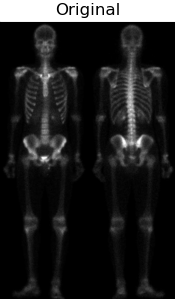

由于对于人体骨骼灰度图的动态范围计较窄,并且噪声比较大,单靠一种滤波或锐化算子无法较好的实现图像的细节增强。故通过设计一种混合的图像增强的方式如下图所示。

根据上图可知,首先通过对原图像img做拉普拉斯算子运算增强突出图像细节,接着将图laplacian与img图像叠加得到图img_laplacian。又因为二阶求导的拉普拉斯算子也会使得图像的噪声增强,而一阶求导的Sobel算子对噪声和小细节的响应较弱。所以通过对原图像img做X和Y两个维度的Sobel算子运算并相加得到图Sobel。进一步可以对图Sobel进行双边滤波,平滑噪声并保留细节,得到图Blur。然后将平滑后的图Blur和图img_laplacian相乘,乘积可以保留灰度变化强烈区域的细节,同时降低灰度变化相对平坦区域的噪声。最后将结果叠加在原图img,并做灰度图幂变化扩展灰度图范围即可得到最终混合增强的锐化图像。

| 最终将各结果进行对比显示 |